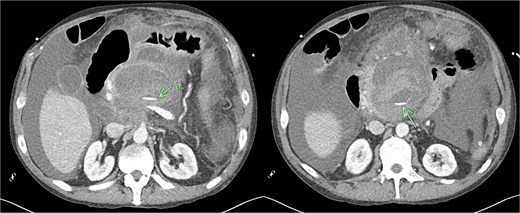

Despite the absence of abdominal symptoms, a computed tomography of the abdomen and pelvis (CTAP) was performed due to markedly elevated lipase levels. The CTAP (Figs 3–5) revealed evidence of acute pancreatitis (Fig. 5, arrow), with a complex peripancreatic fluid collection (Fig. 3, arrow). Additionally, a focal thrombus was observed within the portal venous confluence (Fig. 4, arrow). Further ultrasound of the gallbladder was negative for gallstones (Fig. 6), ruling out gallstone-induced pancreatitis.

CTAP coronal view; complex peripancreatic fluid collection (arrow) with extension behind the splenic vein to lie adjacent to the pancreatic neck and uncinate process.